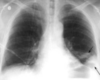

Estudios de imagen en COVID-19

Rx útil en seguimiento, poco sensible al inicio * Hallazgos similares a cualquier neumonía viral * Consolidación en vidrio despulido *Patrón reticular TC mayor sensibilidad + Consolidación periféricas en vidrio esmerilado

COVID-19 con patrón de vidrios despulido

COVID-19 con patrón en vidrio despulido

Vidrio despulido